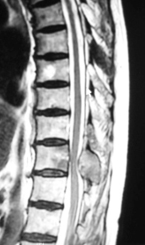

(左)第12胸椎および第1腰椎の骨粗鬆症性椎体骨折を認めます。(中)MRIでは第1腰椎に大きな骨欠損を認め、骨折が難治性で不安定であることを示しています。(右)第1腰椎に椎体形成術を施行し、さらに骨が脆かったため、頭尾側にスクリューを挿入して固定しています。